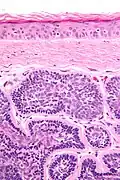

Micrograph of dermal cylindroma in H&E stain.

Dermal cylindromas are:

- Dermal lesions consisting of nests of cells that are surrounded by hyaline (i.e., glassy, eosinophilic, acellular) material and have:

- Hyperchromatic nuclei that may palisade (columnar nuclei arranged around the periphery of the cell nests with their short axis tangential to the nest periphery), and

- Cells with lighter staining ovoid nuclei at their centre.

They lack of a significant number of lymphocytes; this differentiates them from spiradenomas.